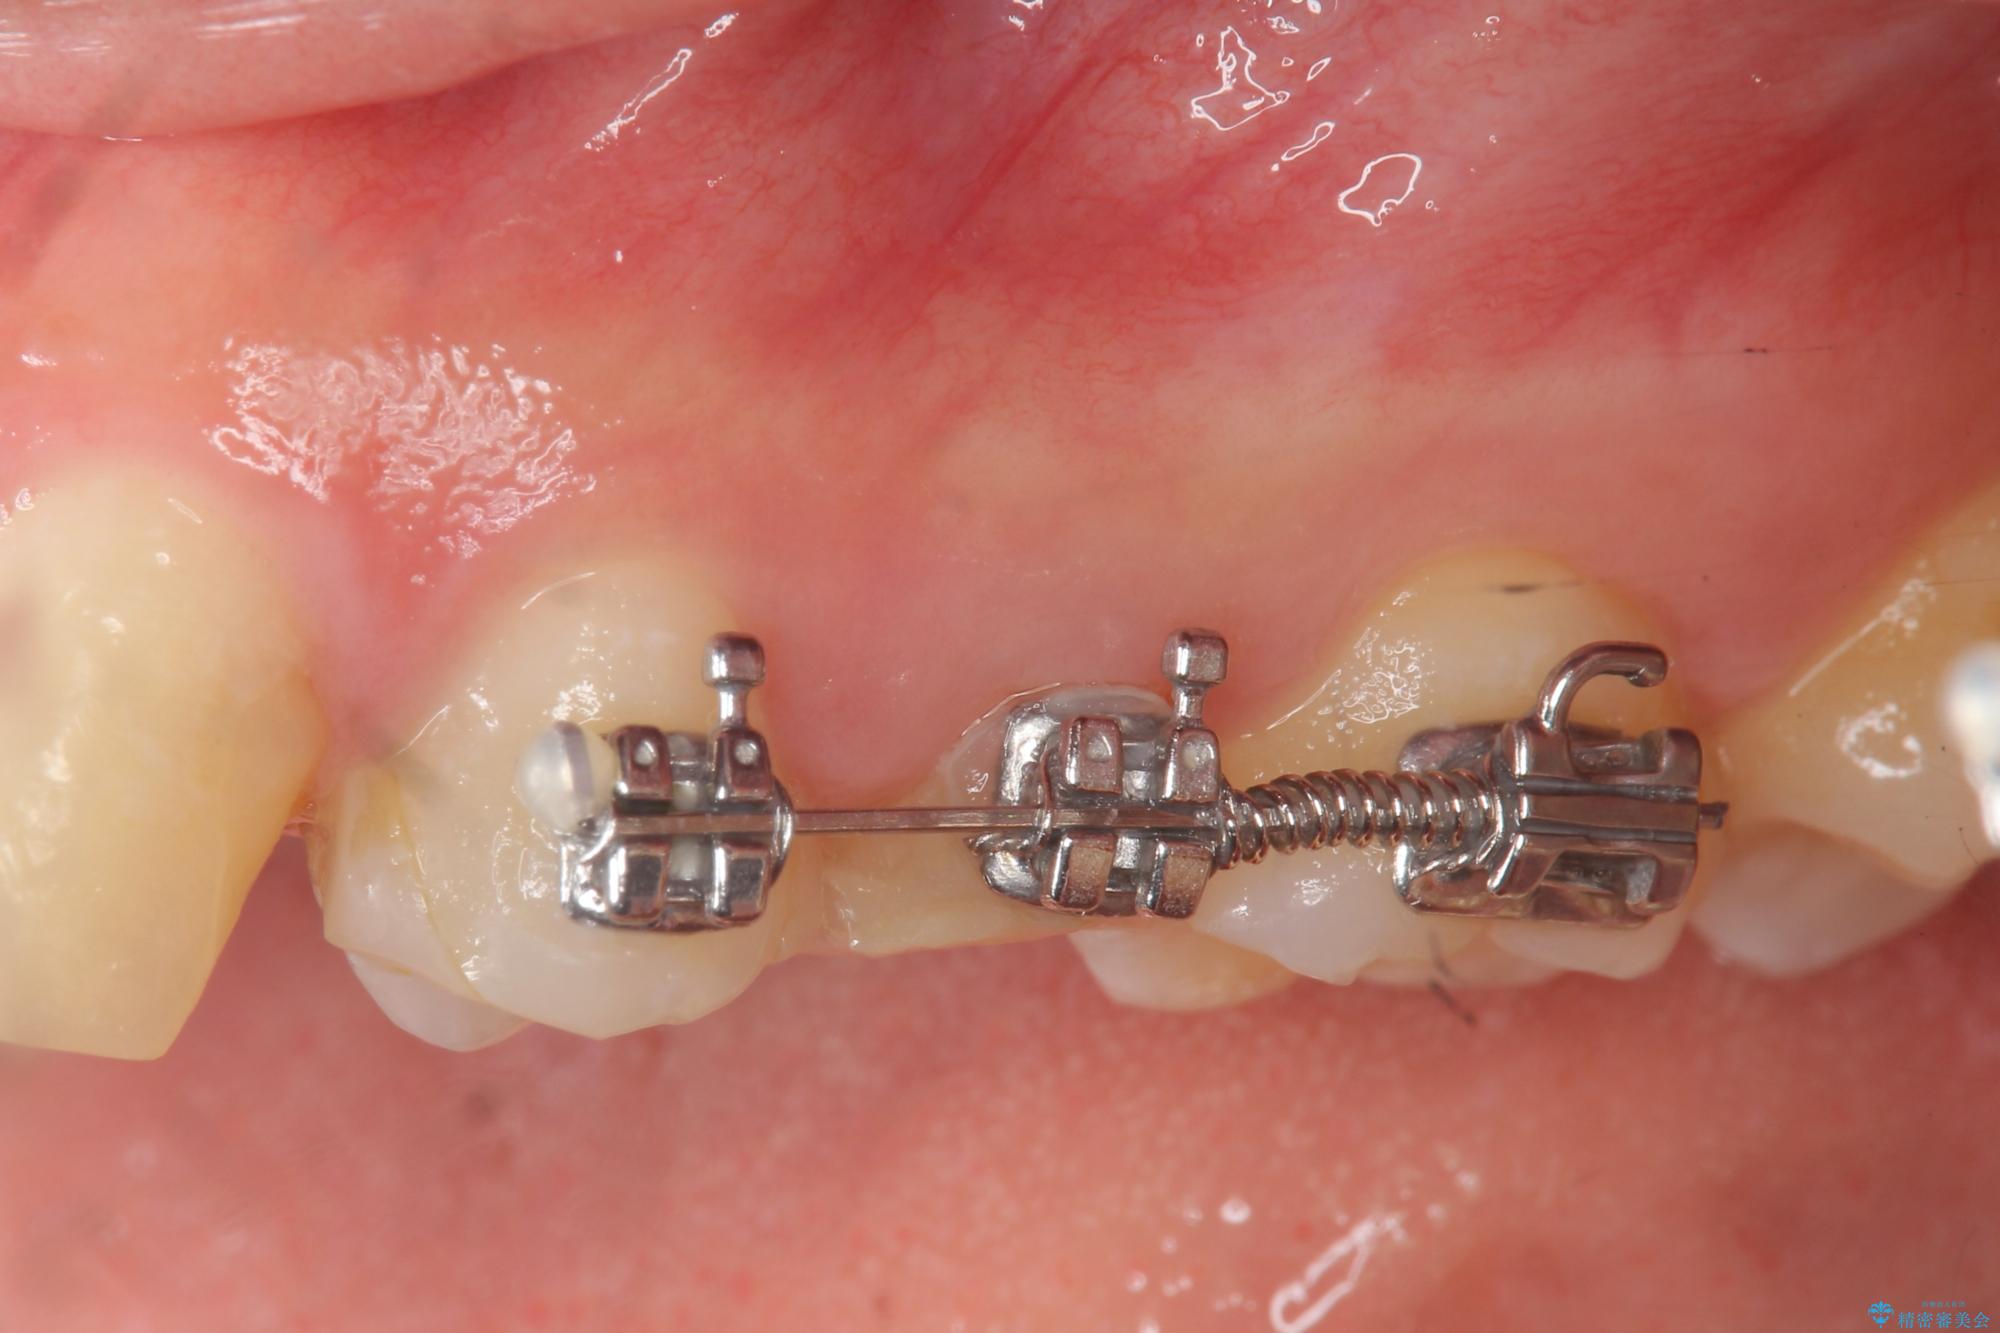

- 部分ワイヤー矯正

- 歯ぐきの腫れや、歯の内部が黒く見えることからの虫歯の治療を求めて来院されました。

虫歯が大きかったことから、神経の温存はできたものの歯ぐきよりも深い虫歯の問題を解決するため部分矯正治療を併用したセラミック治療を行うこととしました。

当初、歯ぐきよりも深い虫歯のぞんざいや、歯のポジションに問題がありましたがマルチブラケットを用いた部分矯正を行うことで適切な位置へと歯を移動させ、歯周環境を整えたセラミック治療を行うことができました。